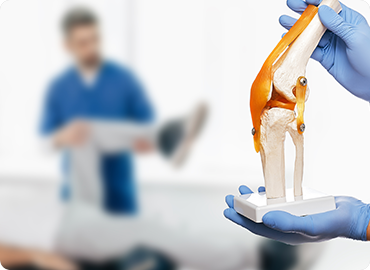

Services We Offer

Broken Bones & Injuries

Diseases & Conditions